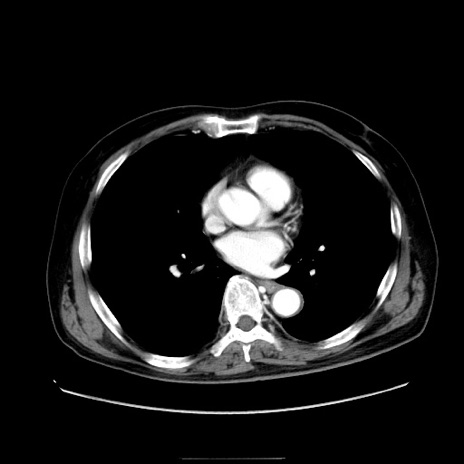

症例30(横断像)

【症例】80歳代男性

【主訴】臍周囲痛

【現病歴】約6時間前から臍下部痛が出現。次第に腹部膨隆・背部痛も生じてきたため来院。背部痛の場所は変化しない。

【既往歴】腎盂腎炎

【身体所見】意識清明、BT 36.3℃、BP  131/87mmHg、P 87bpm、SpO2 100%(RA)、臍周囲自発痛・圧痛あり、反跳痛なし、自発痛部位に一致して板状硬あり、腹部膨隆、腸雑音減弱、CVA tenderness両側陰性。

【データ】WBC 19600、CRP 0.33